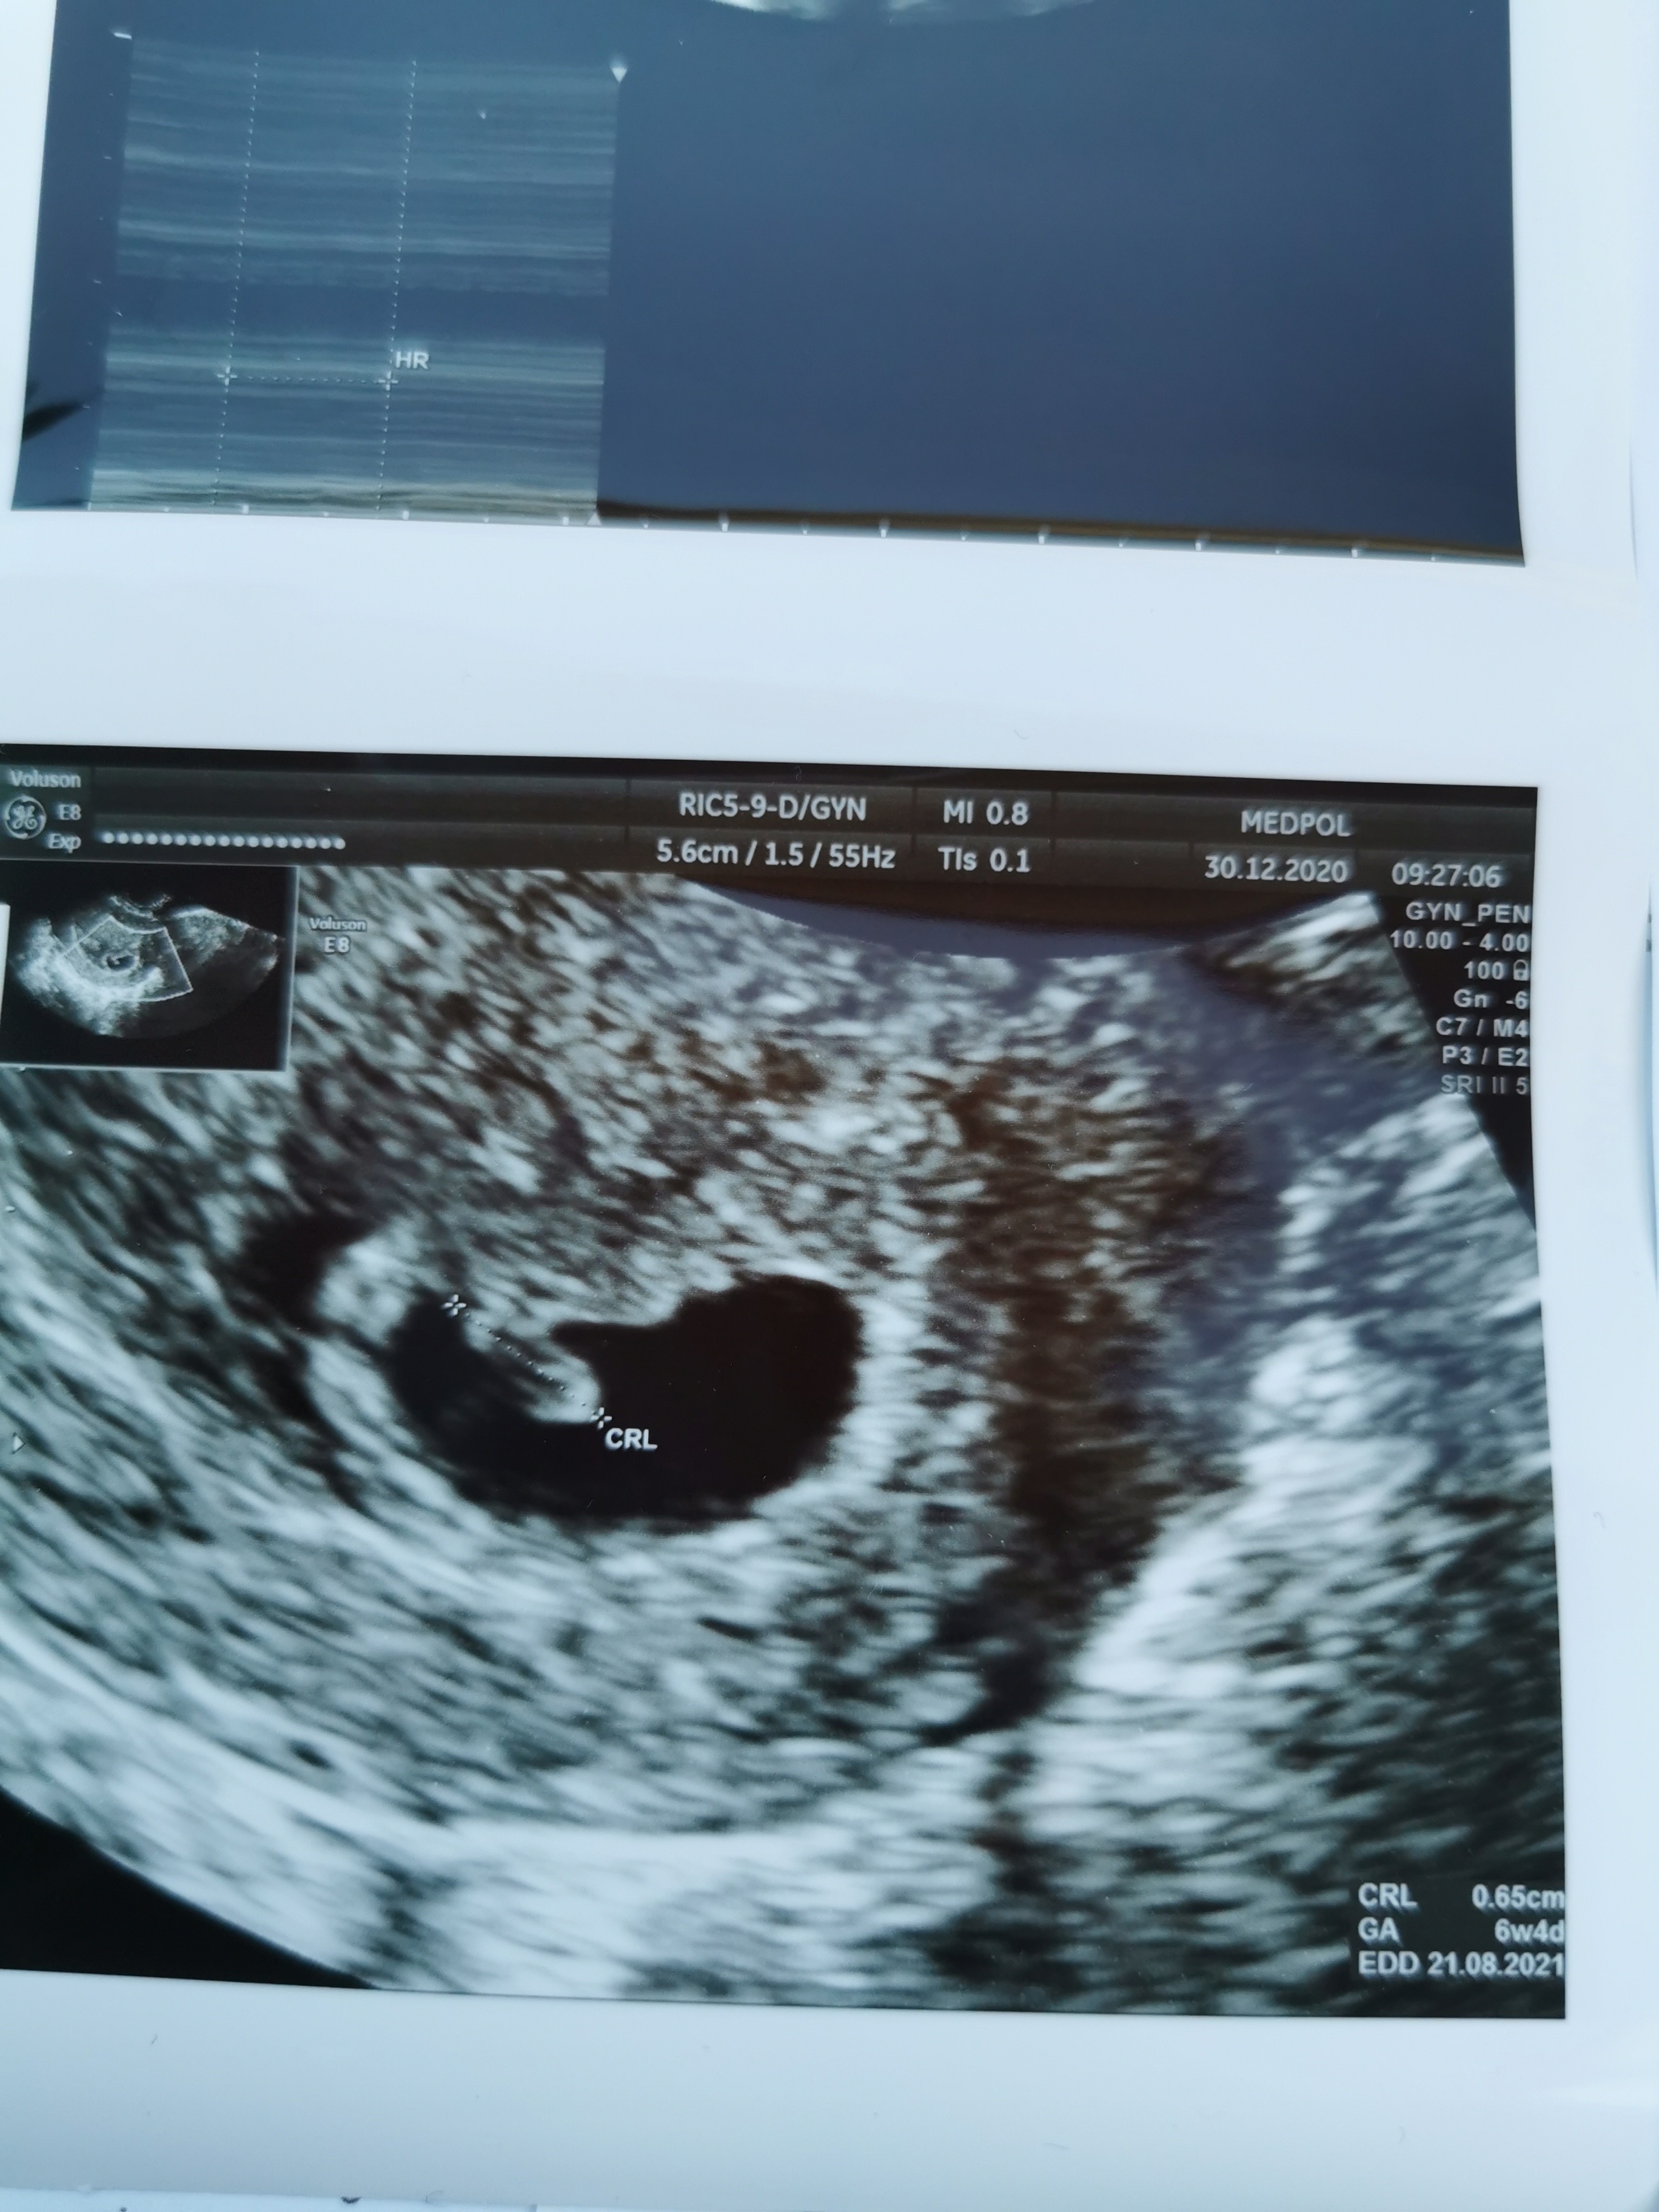

Byłam na wizycie, kropkowi bije serduszko..